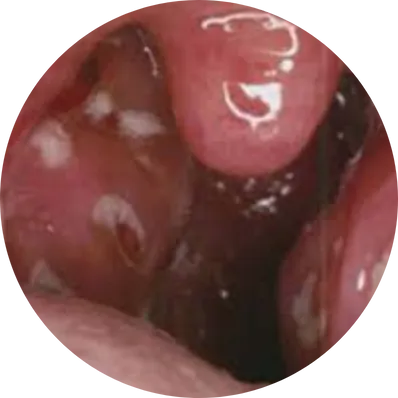

Adenoidectomy is a surgical procedure performed to remove the adenoids – a mass of lymphoid tissue located at the back of the nasal cavity, above the tonsils. While adenoids help fight infection in children, they can become enlarged, chronically infected, or obstructive, causing breathing and ear problems. The surgery is common in children but may occasionally be required in adults.

Adenoidectomy Causes